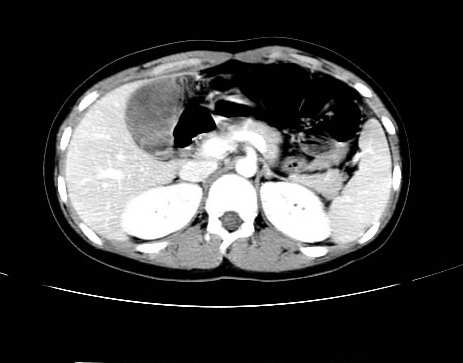

女 16岁  右上腹痛一天,无其他不适

肿块最大径位于十二指肠降段与水平段移行处,并且与肝脏压迹呈“0”形征,可以考虑位于肝外并与胃肠道关系紧密,考虑胃肠道间质瘤(gist)可能较大,须除外神经节起源肿瘤。

肿块与十二指肠关系密切,支持间质瘤诊断.肝脏与结肠均为受压改变.

右下腹巨大肿快,密度不均匀,内见坏死低密度区,边界清楚,与周边胀器明显有分界,未见强化,多考虑来源于间叶组织的良性肿物.

病灶巨大,少部分向肠腔内生长,大部分向长腔外生长。其密度不均匀,增强显示明显不均匀强化,并见有大片状始终不强化的不规则坏死液化区。虽然病灶中上部形态尚可,病人又如此年轻,但中下部形态、密度、强化特点强烈提示为恶性病灶。综上,我考虑本病例为:恶性胃肠道间质瘤。